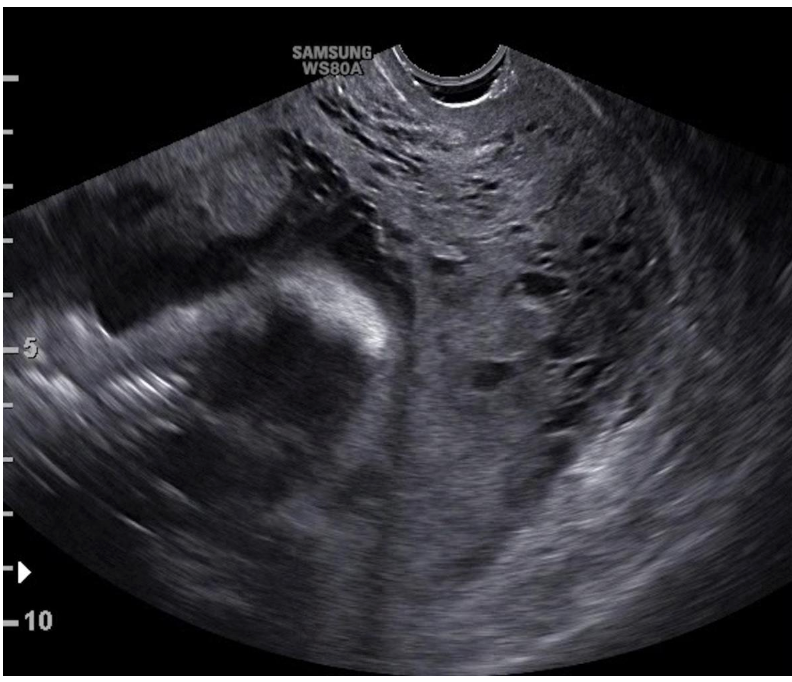

Hình: dấu hiệu “intracervical lakes” trên siêu âm thang xám

Nguồn: ISUOG

Hiện nay, tỷ lệ nhau cài răng lược có khuynh hướng gia tăng, nguyên nhân được cho là do xu hướng gia tăng tỷ lệ mổ lấy thai trên toàn cầu. Chẩn đoán nhau cài răng lược (NCRL) trước sinh có thể làm giảm tỷ lệ tử vong mẹ. Trong thực hành hiện nay, NCRL được chẩn đoán chủ yếu dựa trên siêu âm, ngoài ra cần sự hỗ trợ của MRI trong một số trường hợp khó đánh giá, như nhau bám mặt sau tử cung. Các dấu hiệu “điển hình” chẩn đoán NCRL trên siêu âm bao gồm mất khoảng sáng sau nhau, xoang mạch máu sau nhau, thành bàng quang mất liên tục, tăng sinh mạch máu dựa trên siêu âm Doppler. Tuy nhiên, phần lớn các nghiên cứu đã công bố chỉ đánh giá giá trị chẩn đoán của các dấu hiệu trên siêu âm nhưng chưa xét đến khả năng dự đoán mức độ nặng của NCRL. Ngoài những tiêu chuẩn chẩn đoán đã được công bố, một dấu hiệu mới trên siêu âm vừa được giới thiệu nhằm tăng khả năng chẩn đoán NCRL. Dấu hiệu này được gọi tên là “intracervical lakes”.

Nghiên cứu đi đến kết luận, “intracervical lakes” có thể là dấu hiệu cần lưu ý khi đánh giá mức độ xâm lấn của gai nhau trong các trường hợp nhau tiền đạo. Sự xuất hiện của dấu hiệu này còn có ý nghĩa tiên lượng nặng ở các thai phụ nghi ngờ NCRL.